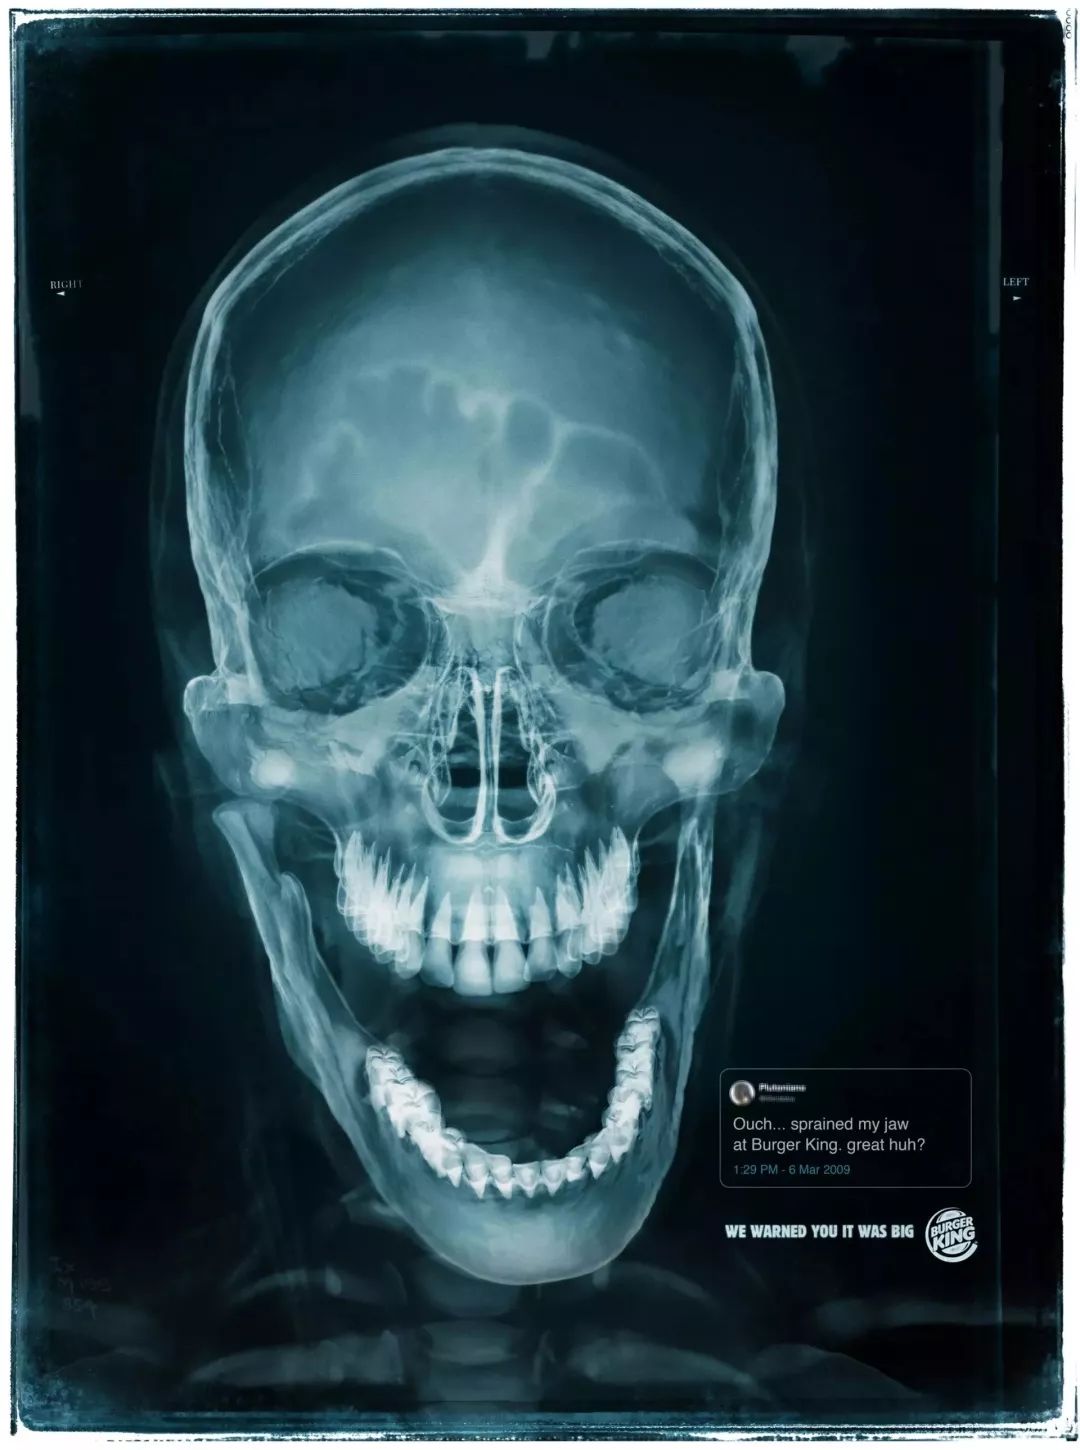

8

<< 滑动查看下一张图片 >>

推完麦当劳,当然不能少了它的对头汉堡王的戏份。汉堡王一直在强调自家的汉堡大,这不,连顾客因为吃自家汉堡导致下巴脱臼的X光都放上来了。把X光片当广告的海报烧脑君还是头回见,结合海报上的温馨提示——“We warned you it was big”,真是让人对汉堡王哭笑不得。